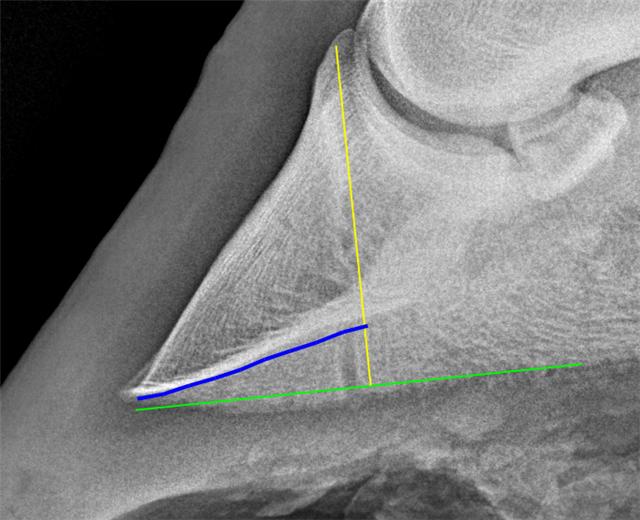

Epona Podiatry Center, LLC Name: Onesy Owner: Ashton Smith Owner ID: Species: Equine Breed: --Unknown--

Sex: --Unknown-Age: 12 Patient ID: Date: 14-Feb-2022